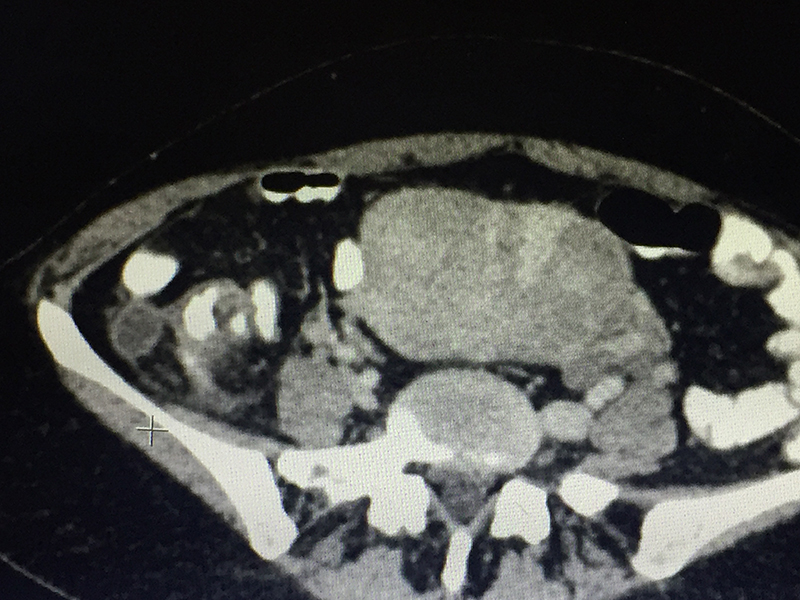

50 year old lady with acute abdominal pain in the right lower abdomen, vomiting and fever was diagnosed with acute appendicitis. Preliminary blood investigations & ultrasonography corroborated the diagnosis. A CT scan of the abdomen and pelvis was done to confirm the diagnosis & look for complications like perforation & abscess. An acute appendicitis with localized perforation & infected fluid collection was observed. She also had a large fibroid in her uterus. As is our policy (most acute appendicitis patients are treated by laparoscopic surgery), patient underwent a laparoscopy. At the time of laparoscopy, a perforated gangrenous appendix was found with a large walled off pus collection in the abdomen. The huge fibroid made the surgery difficult since it kept on coming in the line of surgery. However the appendicectomy was successfully completed laparoscopically and patient was discharged on 4th postoperative day. Due to the existing infection, a hysterectomy for the fibroid was not performed at the same time. It was done later after few months.

When there is a clinical suspicion of acute appendicitis, he / she is subjected to blood (CBC / CRP) investigations and imaging study (Ultrasonography). Severe colitis / enteritis / mesenteric lymphadenitis, ileal perforation, intestinal tuberculosis, inflammatory bowel disease, colonic diverticulitis, pericolic appendagitis, Meckel’s diverticulum etcetera can have present with similar symptoms and signs. Some of these diseases can be managed with medicines alone. Hence a CT scan of abdomen and pelvis with oral and intravenous contrast is advised before any surgery is planned for appendicitis. CT scan not only confirms diagnoses, but also reveals complications like perforation, abscess etcetera or an alternative diagnosis or associated malignancy (as in elderly patients).